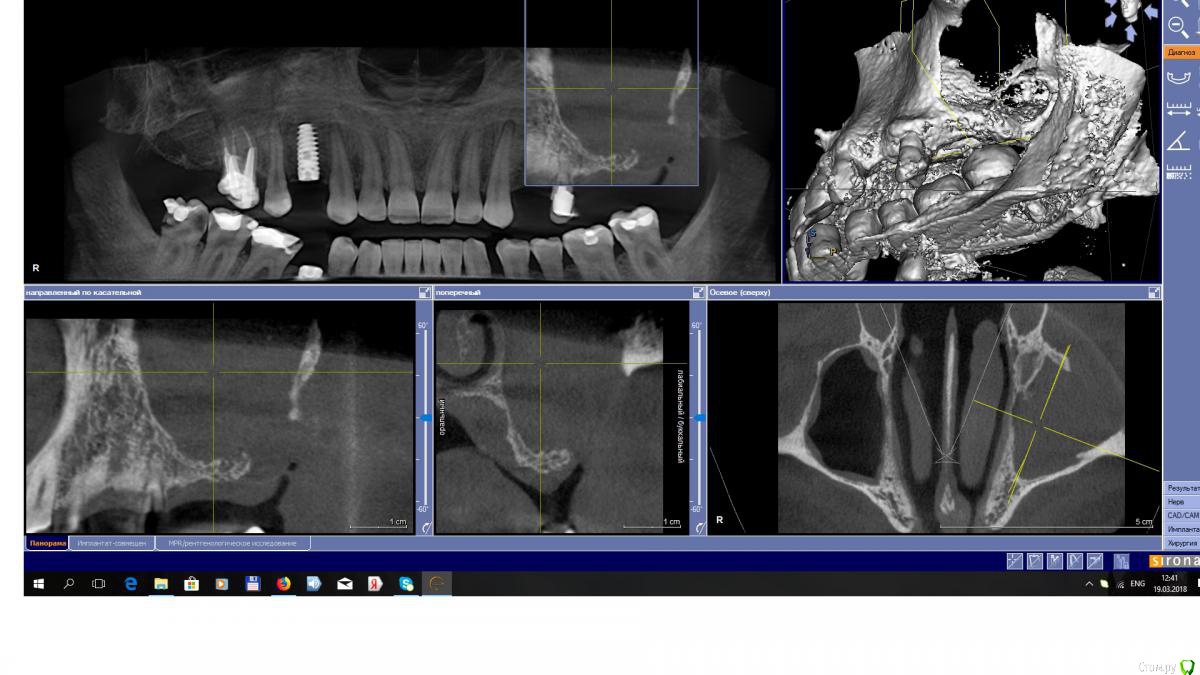

EEcho Опубликовано 19 марта, 2018 Поделиться Опубликовано 19 марта, 2018 Добрый вечер , коллеги.Ваше мнение ?Пациент обратился в 2014г. , поставить импланты во втором сегменте.На КТ обнаружилась такая картина. Был отправлен к ЛОРу. , пациент к нему сразу не пошел, потом и вовсе пропал.А тут появился с желанием опять поставить импланты. новый снимок он пока не делал, и к ЛОРу он то же так и не ходил.Вопрос, что в том случае делать? Ссылка на комментарий

EEcho Опубликовано 20 марта, 2018 Автор Поделиться Опубликовано 20 марта, 2018 Да на реверс , это понятно, Но , если гипотетически, он пойдет к ЛОРу , пролечит пазуху, А дальше?Я делал синус с резными ситуациями, с разными дефектами, опыт есть, но с таким отсутствием стенки пазухи сталкиваюсь впервые.Поэтому в затруднении, как в при таком дефекте закрыть окно, применять ли сетку, или мини пластины, или ламину?Интересно, кто сталкивался с таким, что делал и отдаленные результаты. Ссылка на комментарий

Irouil Опубликовано 20 марта, 2018 Поделиться Опубликовано 20 марта, 2018 (изменено) Найти того, кто готов это разобщить все. Псков недалеко от Петербурга, есть тут один доктор, даже видосики выкладывал со схожими дырками. Ну, или разобщать самостоятельно. Но это все только с условием, что в пазухе действительно рецидив после колдвел/люка, а не онко. Проверьте, кстати, есть там дырка в нижнем носовом ходе? Теоретически ещё могли так 2.8 удалить Изменено 20 марта, 2018 пользователем Irouil Ссылка на комментарий

EEcho Опубликовано 20 марта, 2018 Автор Поделиться Опубликовано 20 марта, 2018 Да Найти того, кто готов это разобщить все. Псков недалеко от Петербурга, есть тут один доктор, даже видосики выкладывал со схожими дырками.Ну, или разобщать самостоятельно. Но это все только с условием, что в пазухе действительно рецидив после колдвел/люка, а не онко.Проверьте, кстати, есть там дырка в нижнем носовом ходе?Теоретически ещё могли так 2.8 удалитьДа, сейчас будем обследовать пациента полностью.подозрение на онко возникло сразу еще 2014 году, но он ни куда не обращался, с тех пор его ни чего не беспокоит, и во рту то же все хорошо.со слов, ему так удалили 28, возможно бугром, после этого он лежал в ЧЛХа , что там делали не помнит.Доктора можно поискать в архиве? Ссылка на комментарий

Bier Опубликовано 23 марта, 2018 Поделиться Опубликовано 23 марта, 2018 посмотрел, мощная дыра. Надо понять, что там в пазухе, если рубцы, но на мой взгляд необходимо на первой операции вычистить пазуху и изолировать ее от полости рта, например, титановой фольгой. На второй операции, после восстановления слизистой проводить синуслифтинг. Ссылка на комментарий